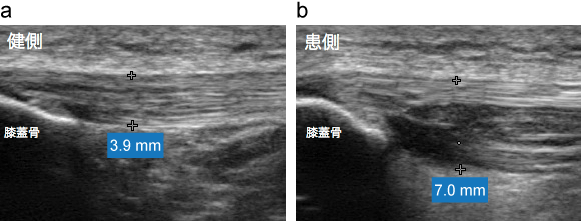

超音波画像(長軸)

膝蓋腱近位部が腫脹し、深層でfibrillar patternの消失が観察される。